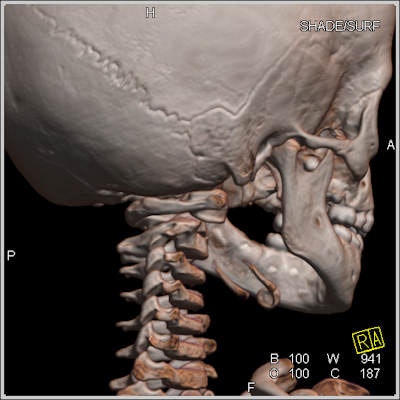

"Donnez-moi vos os et je vous dirai qui vous êtes," a déclaré M. Dedouit, expliquant comment le scanner pouvait être utilisé pour identifier des corps détruits au-delà de toute reconnaissance possible après un accident, ou bien des squelettes retrouvés dans les bois, grâce aux signatures anatomiques telles que des prothèses recensées dans les registres radiologiques, et même des bijoux fondus sur le corps. La moitié des identifications sont réalisées à partir d'archives radiographiques du thorax, un quart à partir de variations dans l'anatomie.